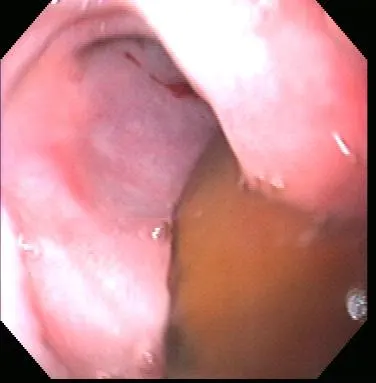

Gastroenteroscopy revealed a hard plastic foreign body (Figure 2) with curved, pointed ends. Points of the object were embedded in the gastric antral mucosa, resulting in hyperplasia. One of the curved points extended through the pylorus and hooked into the proximal duodenum (Figure 3). The endoscope could be passed around the foreign body into the duodenum, allowing biopsy of the duodenal mucosa. The gross appearance of the duodenal mucosa was normal (Figure 4). Attempts to remove the foreign body endoscopically were unsuccessful. Before the dog was sent to surgery for removal of the foreign body, colonoscopy was performed. The colon appeared normal on gross inspection (Figure 5). Biopsies were obtained from the cecum; ascending colon; transverse colon; and proximal, middle, and distal descending colon. At surgery, a gastrotomy incision was made in the pyloric antrum and the foreign body was forcefully removed. It was a plastic object used to secure the legs of a turkey carcass.

Endoscopy of one end of the foreign body hooked around the pylorus